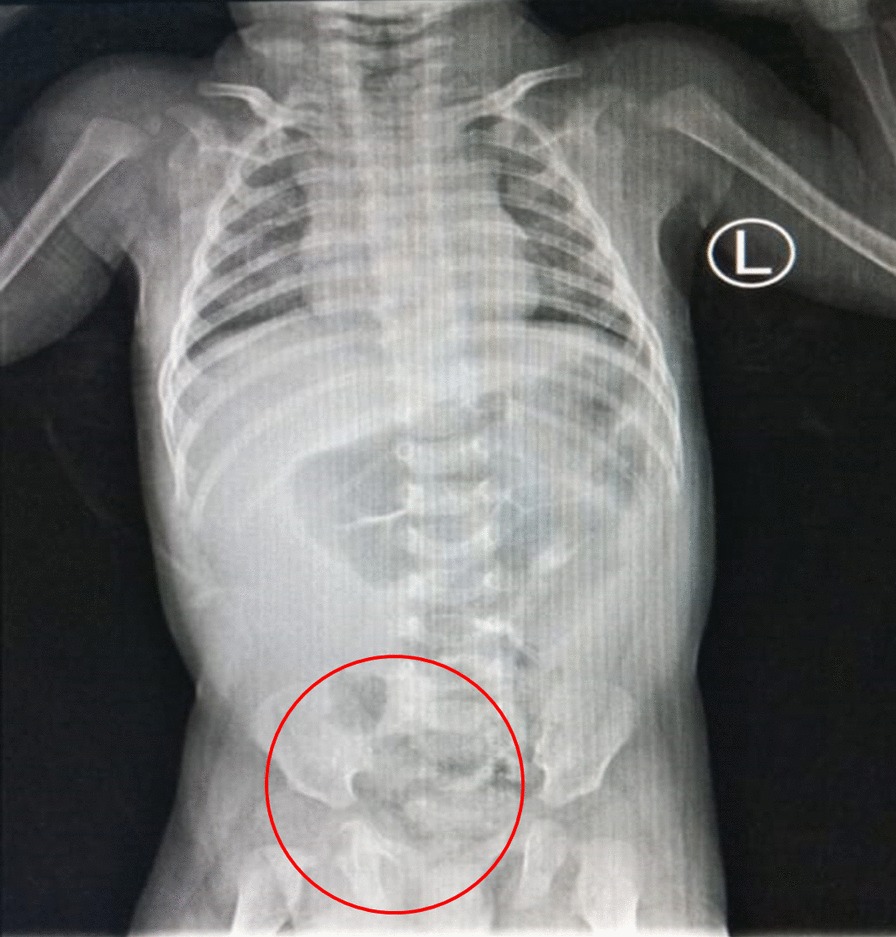

In the emergency department the patient underwent to take plain abdominal radiography. There was intestinal like appearance in the scrotal region and some dilated intestinal but no evidence of intestinal obstruction or aeration in the scrotal compartments (Fig. 2). The advance radiological examination cannot be performed since the patient’s condition. All laboratory values were within normal limits. Based on the clinical examination and radiography the patient was diagnosed with Right Scrotum Hernia. After first initial treatment in the emergency department with normal fluid resuscitation, then patient was planned into laparotomy approach to treat the hernia.

Fig. 2.

Plain abdominal radiography